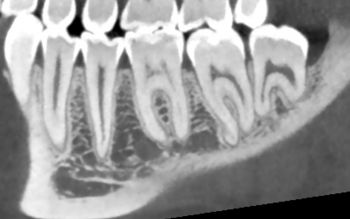

Qu'est ce qu'un Conebeam ?

En quoi consiste l'examen ?

C'est un examen qui est demandé dans les problèmes dentaires, avant une pose d'implant.

L'appareil effectue une rotation autour de vous pour acquérir toute l'arcade dentaire et pour être en mesure de reconstruire les images dans tous les plans de l'espace (3D).

• Une résolution optimale

Longtemps, le scanner était privilégié pour l'étude 3D des massifs dentaires; la technique Conebeam offre aujourd'hui une résolution supérieure au scanner pour ce type d'examen, avec en plus l'avantage de délivrer une dose très faible.